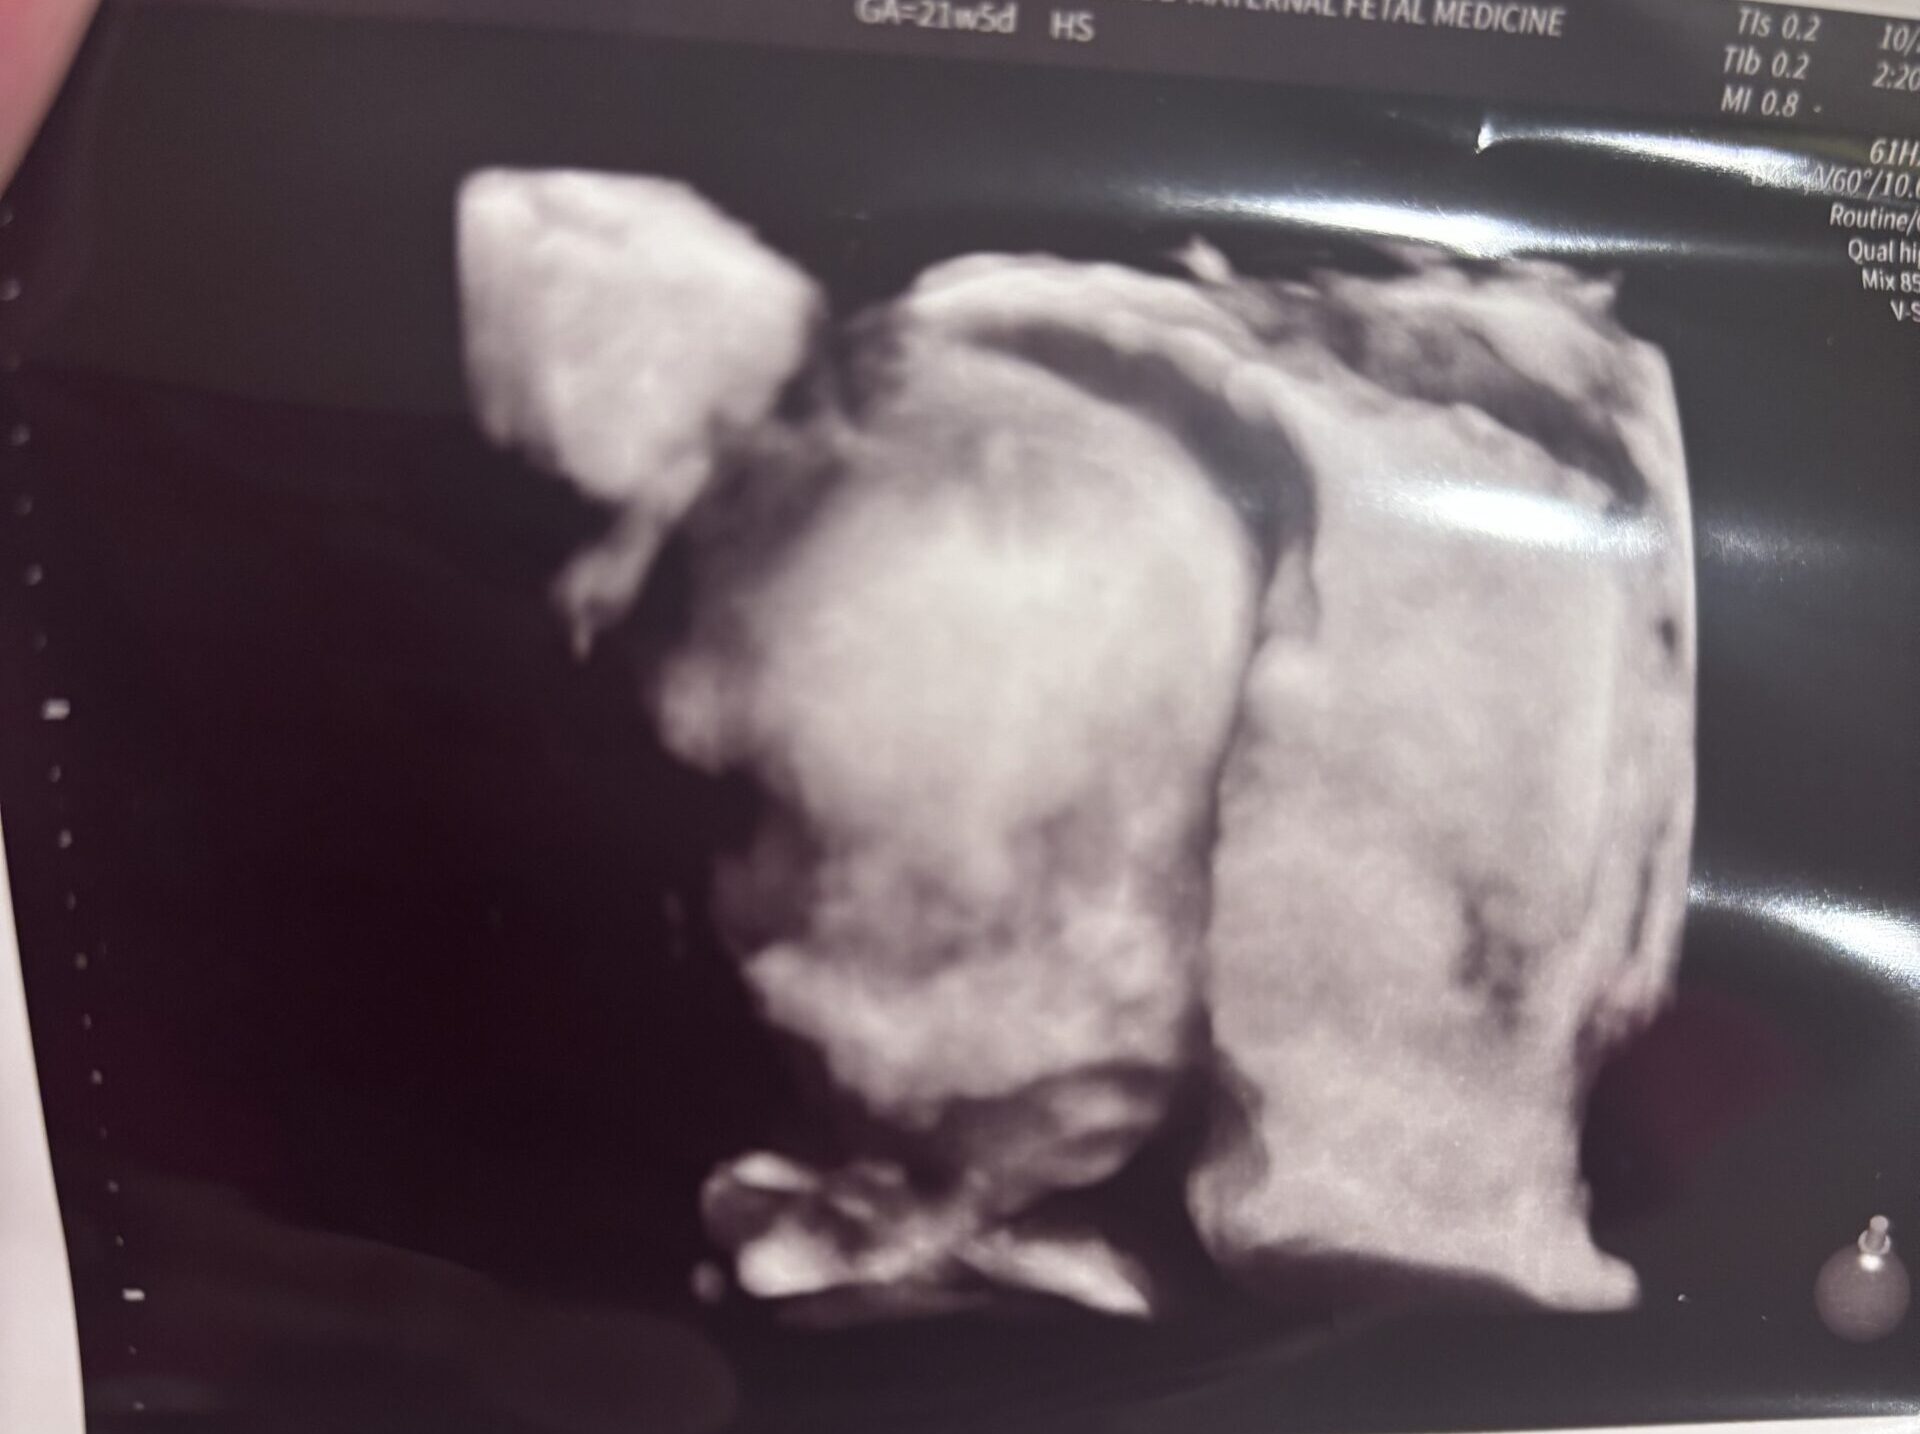

Our little miracle would have never been on the way. Can’t wait for our little guy!!!